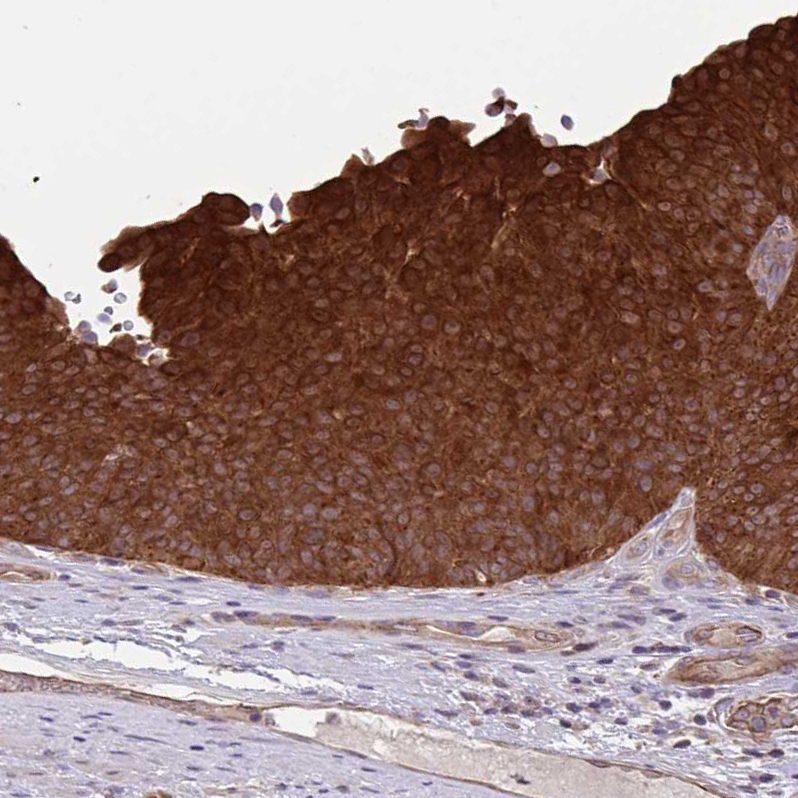

Immunohistochemical staining of human skin shows strong cytoplasmic positivity in squamous epithelial cells.